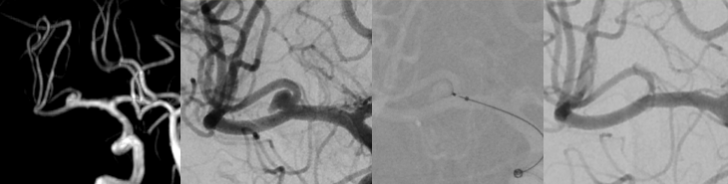

Diagnostically and therapeutically, the most modern methods and equipment are available for our patients. In addition to diagnostic neuroradiology, our clinic is characterized by a high level of expertise in minimally invasive neuroradiological therapy, both in the emergency treatment of strokes and in the elective treatment of aneurysms, vascular stenoses and vascular malformations.